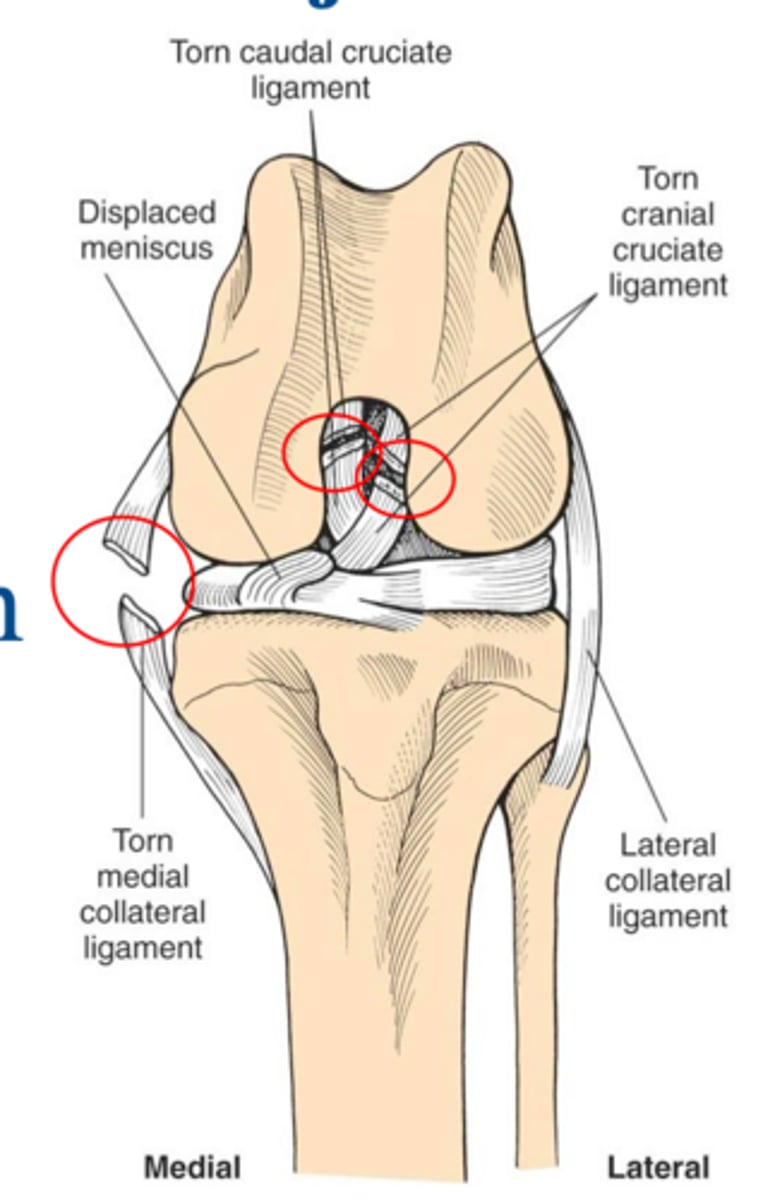

loss of cranial and caudal cruciate lig. and disruption of medial restraints

what damage is notable in this deranged stifle joint

1. cranial and caudal cruciate ligament tears

2. failure of primary and secondary medial restraints

3. peripheral medial meniscal tears

what is the common triad of multiple ligament injuries

deranged stifle...multiple lig. injuries often associated w/ meniscal injury and stifle luxation

what condition is shown here